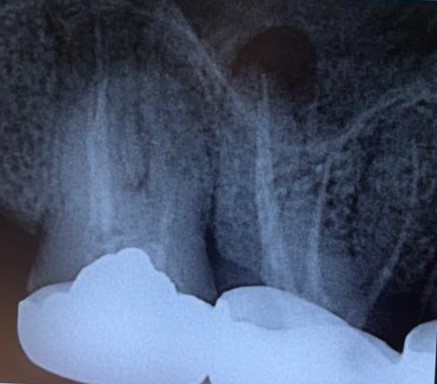

4. Radiographic Examination

- Periapical X-ray of Tooth #17

5. Diagnosis

- Chronic Periapical Abscess (Tooth #17)

- Failed Previous Root Canal Treatment

- Missed Buccodistal (BD) Canal

- Missed Mesio-Buccal 2 (MB2) Canal